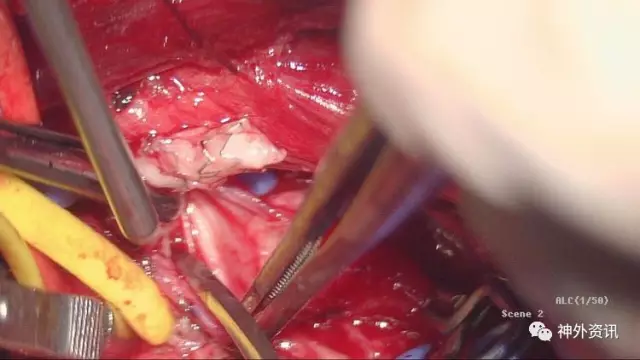

术中视野

这个是左侧椎动脉三角的解剖:由于左椎开口位置深在,前方有胸导管横过,毗邻神经血管丰富,手术操作较右椎A开口段手术要困难一些,病人胸导管损伤、膈神经牵拉副损伤、胸膜顶损伤致气胸的风险较高,因而手术要求熟悉局部解剖,有较好的显微操作基础

赵鹏博士在做手术显露,病人服着单抗,这个层次很明晰,手术视野基本是无血手术,这样的术野你能看到每一条血管和神经,术中副损伤和意外情况会降到最低

从胸锁乳突肌内外侧头之间纵行分开肌束,观察内部结构,这个术野依然是那么清晰

在肌肉下方我们发现了横向外下的胸导管,黄箭头所示

充分游离、显露ⅤA起始段,锁骨下动脉向内外显露各约1.5cm,于血管下留置橡皮条,以方便术中阻断

标记VA内置支架段内膜剥离直切口,阻断锁骨下动脉远近端,马上可以切除支架了

切开外中膜,先切开支架远端管腔,手术的关键是摘除支架,而远端血管通畅我们的手术会更有把握,刀尖切到之处有颅内反向血流溢出

切开外膜你看到了M,亮晶晶的金属支架嵌入增生内膜

支架马上就摘除了,成功在望